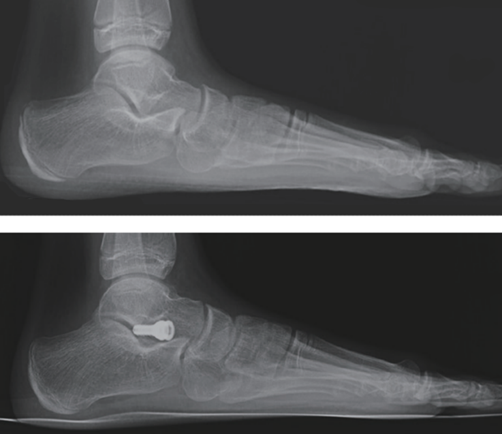

图13:侧位X光片,下方为术后。

图14:跟骨轴位X光片,右侧为术后,跟骨外翻已纠正。